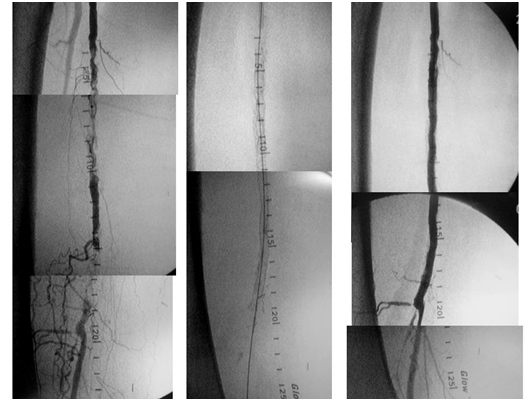

estudio_arterial por admin | Ago 30, 2016 | 0 Comentarios Recanalización endovascular compleja mediante Stent en paciente portador de by-pass distal Enviar comentario Cancelar la respuestaTu dirección de correo electrónico no será publicada. Los campos obligatorios están marcados con *Comentario * Nombre * Correo electrónico * Web Guarda mi nombre, correo electrónico y web en este navegador para la próxima vez que comente. Δ